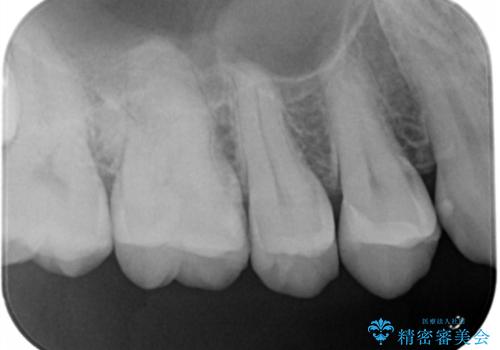

- 虫歯がないかチェックしてほしいとの事で来院。

レントゲンで歯と歯の間に虫歯(コンタクトカリエス)があったので

拡大鏡下で虫歯を全て除去して、e-maxインレーにて治療しました。